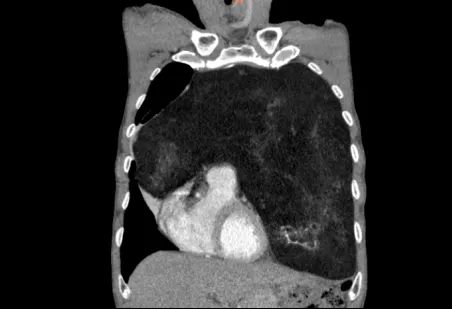

怀着忐忑的心情,家人陪同老人来到郑州大学第五附属医院胸外科就诊。完善胸部增强CT检查后,结果让经验丰富的高兴才主任也为之震惊:患者的前纵隔、左侧胸腔乃至部分右侧胸腔,被一个巨大的混杂密度团块所占据,其长径达23cm!这个巨大的瘤体几乎占满左侧胸腔,严重挤压纵隔使其向右移位,左肺因受压而萎陷。这正是导致老人长期胸闷、呼吸不畅的“罪魁祸首”。

在胸外科医护团队的精心治疗与护理下,老人术后恢复顺利,胸闷症状完全消失,各项生命体征平稳,对恢复情况非常满意。术后病理结果证实为纵隔脂肪肉瘤,但由于手术切除完整,为老人的长期预后和高质量生活奠定了坚实基础。